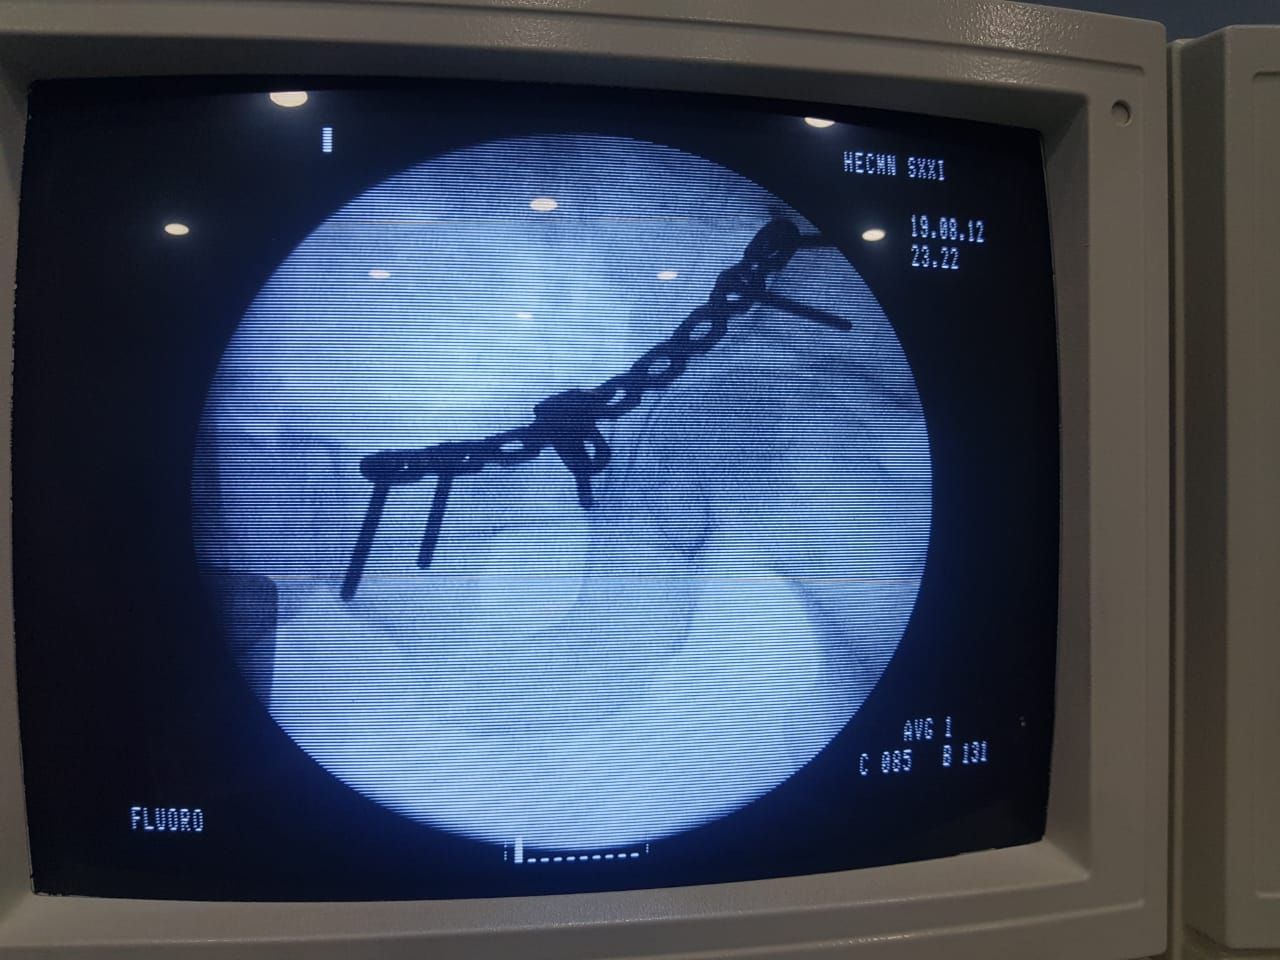

Alta Especialidad en cirugia de Cadera y Pelvis.

- Reemplazo articular de cadera

- Artroscopia y lesiones deportivas

- Reconstrucción articular